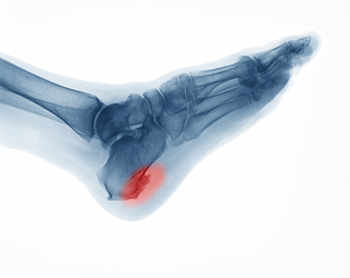

Understanding Plantar Fibromatosis

Understanding Plantar FibromatosisPlantar fibromatosis is a condition where benign, firm nodules develop in the plantar fascia, the thick band of tissue along the bottom of the foot. These nodules are typically slow-growing and non-cancerous but can cause discomfort...